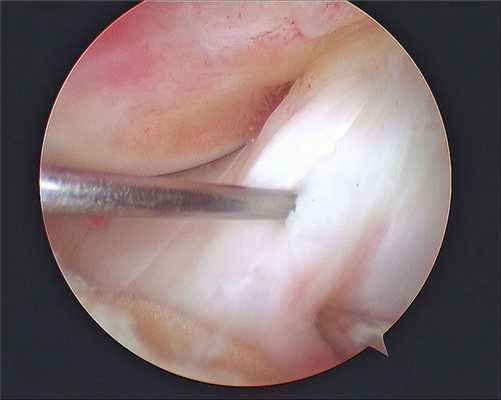

• Циклоп-синдром:

о Резекция направлена на полное выздоровление

• Соударение в области вырезки:

о «Пластика вырезки» открытой передней верхней поверхности вырезки и облегчение соударения